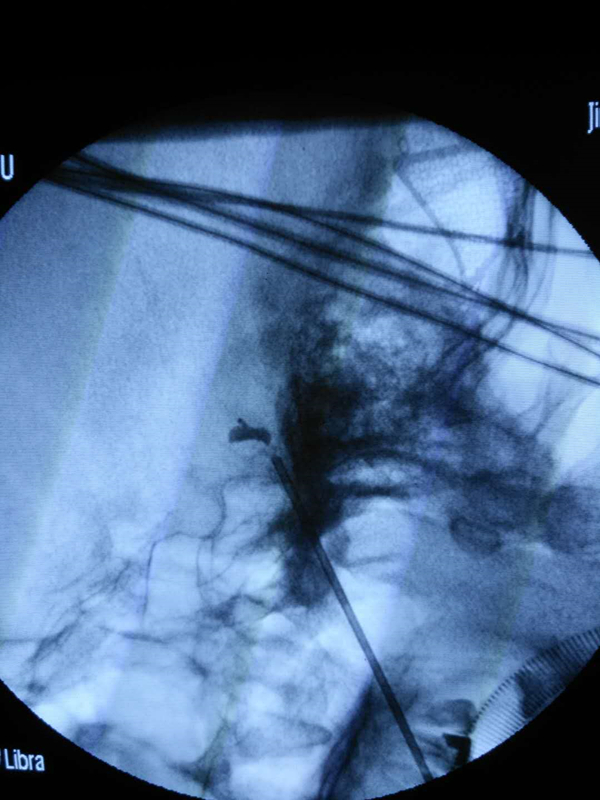

一个球囊、一个针眼,不到一个小时,困扰患者半年三叉神经痛就被消除了。日前,济宁市第一人民医院成功完成鲁西南首例独立开展的经皮穿刺球囊压迫治疗三叉神经痛手术,标志着该院治疗三叉神经痛技术水平再上新台阶,也让无法或不愿进行开颅手术的患者来院治疗时又多了一种选择。创口小、恢复快,一小时去除困扰半年痛苦。

3月5日,马先生再次来到市一院就诊,神经外科副主任、功能神经外科赵长地教授对患者的身体状况进行了观察评估,决定于3月6日采用经皮穿刺球囊压迫方法进行治疗。手术进展得很顺利,全程不到一个小时,患者术后恢复良好,原三叉神经痛完全消失了,在经过两日休养后于3月8日出院。“手术创口很小,回到家这几天都没觉得疼,个人感觉手术效果还不错。”接受术后回访时,马先生对于市一院医护人员的精良医术给予了充分肯定。

据赵长地介绍,穿刺球囊压迫无需开刀,只需在患者嘴角边上穿刺,将球囊插入卵圆孔,对三叉神经半月节进行压迫治疗。和传统显微血管减压术相比,穿刺球囊压迫具有创口小、无切口、无需开颅、术后恢复时间短等优势。“有的患者因为年龄偏大、心脏不好或者患有心脑血管疾病,不适合采用微血管减压术进行治疗;一些患者因为心理畏惧,不愿意接受开颅手术,在这种情况下,穿刺球囊压迫更加适用,也让这些患者在进行治疗时多了一种选择。”赵长地说。